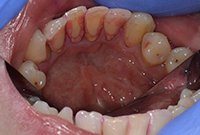

Удаление коричневого зубного налета

Профессиональная гигиена полости рта с целью удаления коричневого зубного налета у мужчины 37 лет.

Удаление коричневого зубного налета До

Удаление коричневого зубного налета После